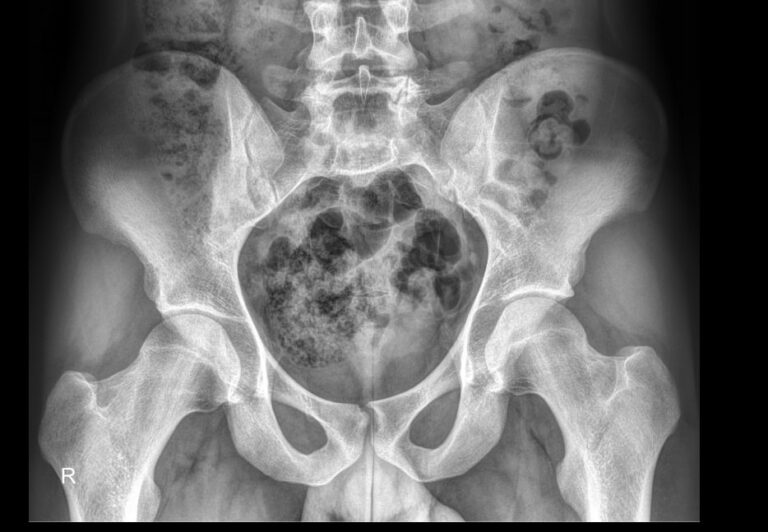

Что показывает обзорный рентген малого таза

На снимке будут видны изменения в костной ткани:

- Переломы, трещины и обломки костей;

- Частично обызвествленные новообразования;

- Участки других патологических процессов ― разрежения костных структур, гнойного расплавления, склероза;

- Патологию тазобедренных суставов;

- Значительные кровоизлияния и участки воспаления.

В области мочевого пузыря могут быть обнаружены конкременты ― камни. В мягких тканях ― опухоли.